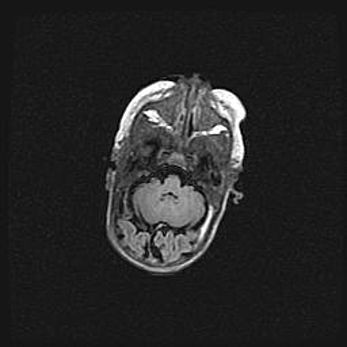

Мальформация Денди-Уокера. Киста задней черепной ямки.

Агенезия мозолистого тела.

Возраст: 2,5 месяца

Вес: 2420 г

Пол: женский

Окружность головы: 37 см

Срок гестации: 32 недели

Мальформация Денди—Уокера — редкий вид патологии ЦНС, представляющий собой врожденный порок развития каудального отдела ствола и червя мозжечка, ведущий к неполному раскрытию срединной (Мажанди) и латеральных (Лушка) апертур IV желудочка мозга. Для этогно синдрома характерна триада симптомов: гипотрофия червя мозжечка и/или полушарий мозжечка, кисты задней черепной ямки, гидроцефалия различной степени. В 70% случаев порок сочетается и с другими аномалиями головного мозга, в частности с агенезией мозолистого тела.